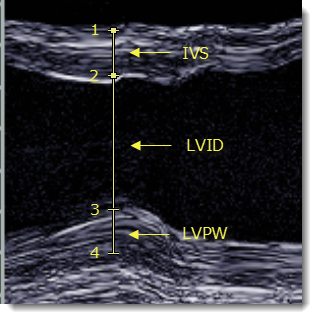

Χρησιμοποιήστε το εργαλείο Απόσταση LV για να μετρήσετε το μεσοκοιλιακό διάφραγμα (IVS), την εσωτερική διάσταση αριστερής κοιλίας (LVID) και το πάχος οπίσθιου τοιχώματος αριστερής κοιλίας (LVPW) σε εικόνες υπερηχογραφήματος M-mode.

- Κάντε κλικ στο ένα άκρο του IVS για να τοποθετήσετε την πρώτη λαβή (1).

- Κάντε κλικ στο άλλο άκρο του IVS για να τοποθετήσετε τη δεύτερη λαβή (2).

Εμφανίζεται το πάχος του IVS.

- Κάντε κλικ στο ένα άκρο του LVPW για να τοποθετήσετε την τρίτη λαβή (3).

Εμφανίζεται το LVID.

- Κάντε κλικ στο άλλο άκρο του LVPW για να τοποθετήσετε την τέταρτη λαβή (4).

Εμφανίζεται το πάχος του LVPW.